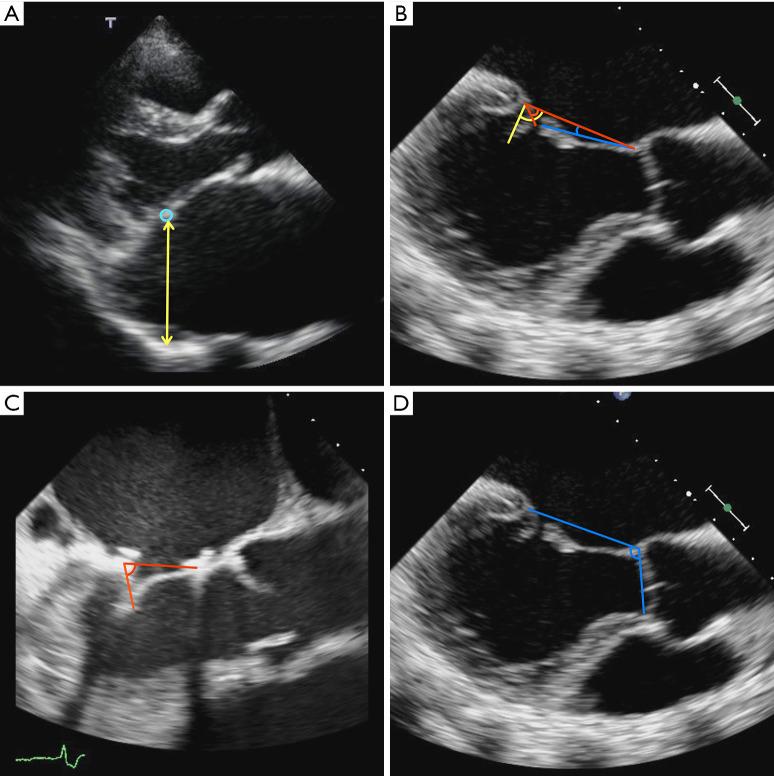

All patients underwent mitral annuloplasty. Of these, 26 underwent additional LA plication. In the mid-term periods, protruding posterior LA length in patients with LA plication was shorter than those without LA plication (2.8±0.49 . 3.3±0.72 cm, P=0.01). The percentage change in aortomitral angle from preoperative to mid-term periods in patients with LA plication was bigger than those without LA plication (1.04°±0.102° . 0.98°±0.084°, P=0.01). Posterior leaflet coaptation angle in patients with LA plication was smaller than those without LA plication (42°±15° . 76°±30°, P<0.001). A postoperative posterior leaflet coaptation angle of 101° had the maximum sum of sensitivity and specificity in predicting postoperative CVEs (96.9% and 76.9%, respectively). Patients with a postoperative posterior leaflet coaptation angle of 101° or higher had a poorer prognosis than those with an angle less than 101°, with an event-free rate of 18% . 80% at 7 years after surgery (P<0.0001).

所有患者均接受二尖瓣环成形术。其中,26例患者接受了额外的左心房折叠术。在中期,行左心房折叠术患者的左心房后凸长度短于未行左心房折叠术的患者(2.8±0.49对3.3±0.72cm,P = 0.01)。行左心房折叠术患者从术前到中期主动脉二尖瓣角的百分比变化大于未行左心房折叠术的患者(1.04°±0.102°对0.98°±0.084°,P = 0.01)。行左心房折叠术患者的后叶对合角小于未行左心房折叠术的患者(42°±15°对76°±30°,P<0.001)。术后后叶对合角为101°时,预测术后心血管事件的敏感性和特异性之和最高(分别为96.9%和76.9%)。术后后叶对合角为101°或更高的患者预后比角度小于101°的患者差,术后7年无事件发生率为18%对80%(P<0.0001)。